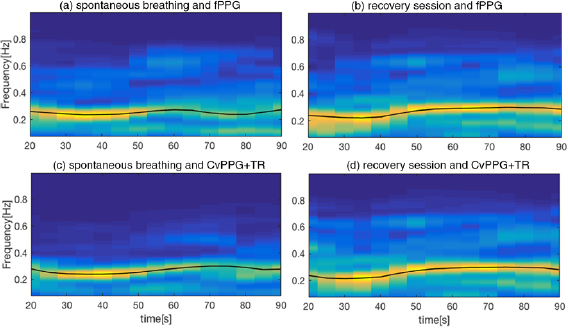

An example of time frequency analysis is shown in figure 6, where the stages of spontaneous and recovery breath are shown for the fPPG (figure 6(a) and figure 6(b) respectively) and vPPG (figure 6(c) and figure 6(d), respectively). As can be seen, the two methods show similar behavior in the respiratory rate tracking over the time.

Figure 6. ((a), (c)) Time–frequency analysis,  , of DR signals during the spontaneous breathing session for fPPG and CvPPG+TR respectively; ((b), (d)) time–frequency analysis of recovery session of fPPG and CvPPG+TR, respectively. The black line represents the estimated BR evaluated on a 10 s running window.

, of DR signals during the spontaneous breathing session for fPPG and CvPPG+TR respectively; ((b), (d)) time–frequency analysis of recovery session of fPPG and CvPPG+TR, respectively. The black line represents the estimated BR evaluated on a 10 s running window.